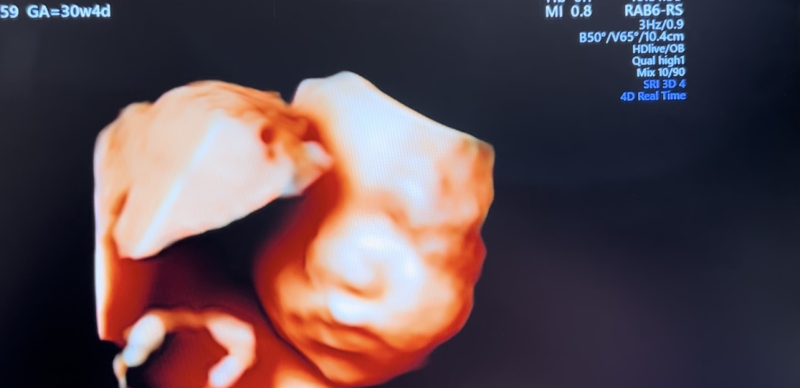

妊婦健診で4Dのエコー写真を撮って頂けるのですが、

顔の特徴がダウン症の特徴と同じのような感じがして

不安です。鼻は低いし目がつり目?のような浮腫んでるような…。

※写真は28週、35週、32週の順です。

実際にエコー写真でダウン症顔貌かの判断は、できないかなと思います。私からみて、エコーでみる赤ちゃんの顔としては、特徴的な顔貌の印象はないです。

エコー画像は、実際に見る感じとは、少し違う感じに見えるかなと思います。